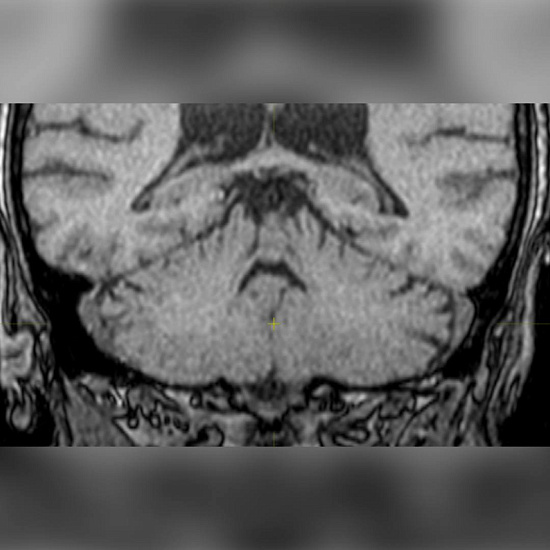

• МРТ ГМ: участок кистозно-глиозного изменения в правой теменной доле. Единичные очаги сосудистого генеза. Изменений в артериях нет. Синусы и внутричерепные вены без особенностей.